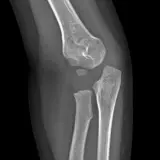

Over 2,100 interactive radiology cases, curated by radiologists for your level of training. Scroll, window, and view cases full screen — just like on PACS. Click linked findings in each writeup to jump straight to them on the image. Cases include sample reports, a focused discussion section, original illustrations, and videos.

PACSで期待されるツールを完備した完全インタラクティブな症例 — スクロール、ウィンドウ調整、ズーム、パン、計測、ROI、フルスクリーンモード。

重要な所見を症例画像上に直接ハイライトする豊富なアノテーション。症例解説内のリンクされた所見をクリックすると、スキャン上の正確な位置へジャンプできます。

職場のPACSステーションと同じようにスクロール、パン、ウィンドウ調整、ズームが可能

アノテーション付きの画像所見とイラストで効率的に学習